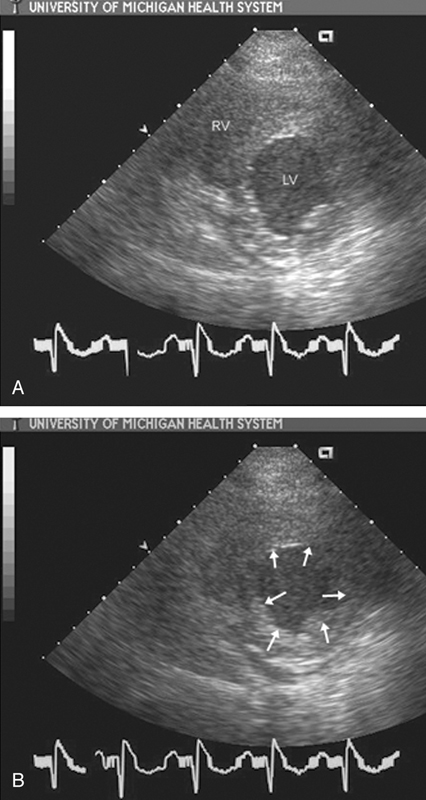

فحوصات تشخيصية لبعض امراض القلب والشرايين التاجية